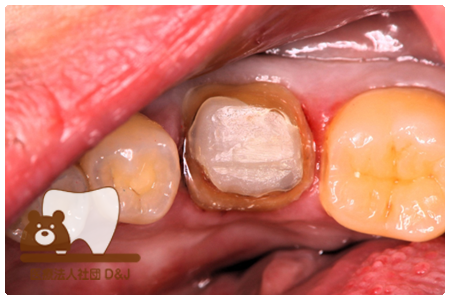

症例3フリジルコニアクラウン 左上6

治療前

治療後

59歳 男性

- 治療内容

- 虫歯で大きく失われた歯に対して、土台としてファイバーコアを使用し、その上にフルジルコニア製の被せ物を装着しました。見た目と強度を両立した自由診療の治療です。

- 治療期間

- 根の治療含めて3カ月半

- 費用

- 自費

フリジルコニアクラウン:77,000円(税込)

(R8.2月時点)

- その他の治療の費用は含まれておりません。

- リスク・副作用

- 強い力が加わると割れる可能性があります。また、噛み合わせや歯ぎしりの影響で脱離することがあります。